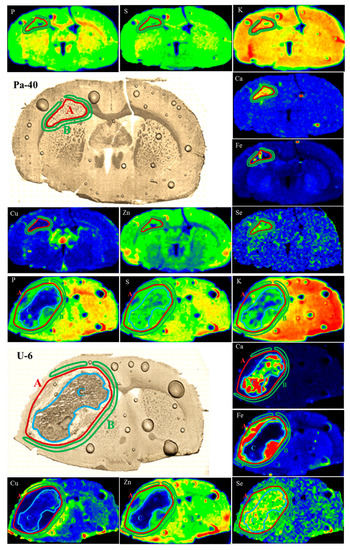

First, based on the microscopic images of the tissues for the Pa and U groups, the areas corresponding to the place of tumor development were defined. When choosing the areas of interest for the samples originating from the M and T groups, we based the selections on the regions with the increased Fe accumulation that correlated with the places where T98g cells or DMEM were administered. For the brain samples taken from the rats representing the M, T and Pa groups, we defined two regions: first corresponding to the places where the medium or glioma cells were administered and second constituting their surroundings. In the case of the tumors developed from U87mg cells, due to the clear heterogeneity within their structure, we also defined an additional region inside the tumor bulk, which is further referred to as the tumor debris. The mentioned areas, marked in the elemental maps and microscopic images of the selected samples representing the Pa and U groups, are presented in Figure 4.

Figure 4.

Regions of tumor (A), surrounding tissue (B) and tumor debris (C) marked in the maps of elemental distribution as well as microscopic images of brain slices taken from selected animals representing Pa and U groups.

As one can see from Figure 5, the tumors developed after the implantation of U87mg cells presented numerous statistically significant differences in the elemental distribution, both comparing to their surrounding and within the tumor bulk, which resulted from their heterogeneous structure. Defined for the U group, tumor debris was characterized by the diminished quantities of P, Fe and Zn compared both to the tumor as well as to the tissue adjacent tumor. Furthermore, in this region, we observed a reduced accumulation of Cu and an increased content of Ca and Se, in relation to the surrounding tissues.

The comparison of tumors developing in the animals representing the Pa and U groups showed a similar pattern of elemental differences between the tumor and its surroundings. The tumors developed from both U87mg cells and from patient-derived cells were characterized by a higher accumulation of Fe and Se compared to the adjacent tissues. In turn, the tumor’s surroundings revealed an elevated content of Cu in relation to its bulk. Additionally, the M and T groups were similar one to the other in terms of the observed elemental anomalies. The places where the T98g cells or DMEM were administered presented an elevated Ca and Fe accumulation compared to the surrounding tissue.

Fe accumulation changes at the place of administration were common for the samples taken from all the experimental groups and the amount of this element was always higher there in relation to the surroundings.